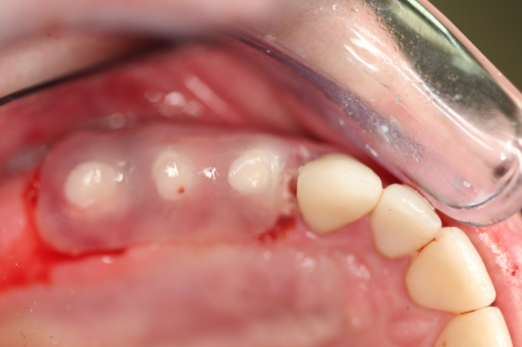

Fig 2. Extractions and immediate placement.

Figure 2

Figure 1 and Figure 2 depict the preoperative image and subsequent removal of three posterior teeth, immediate placement of zirconia-oxide ceramic dental implants, and soft-tissue augmentation with platelet-rich fibrin (PRF) to enhance the soft-tissue architecture surrounding the ceramic implants. The teeth were removed atraumatically and without suture placement. Because the implants were one-piece in stature (the abutment was incorporated into the implant), the recommendation was to splint the multiple units to minimize the lateral forces from mastication, swallowing, and tongue movement.